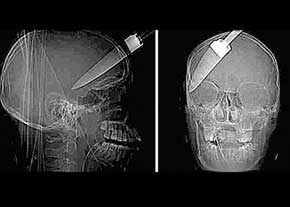

اين در حاليست كه تصاوير X-RAY گرفته شده از جمجمه اين مرد نشان از اين دارد كه اين چاقو تا عمق جمجمه وي فرو رفته، اما هيچ آسيبي به غشاي مغزي اين مرد وارد نيامده است.

براساس اعلام پزشكان معالج اين مرد، چاقوي مذكور از نزديكي گوش اين مرد وارد جمجمهاش شده و تا نزديكي دهان وي فرو رفته است. با اين حال تنها چند رگ و عصب در محل فرو رفتن اين چاقو بريده شده است.